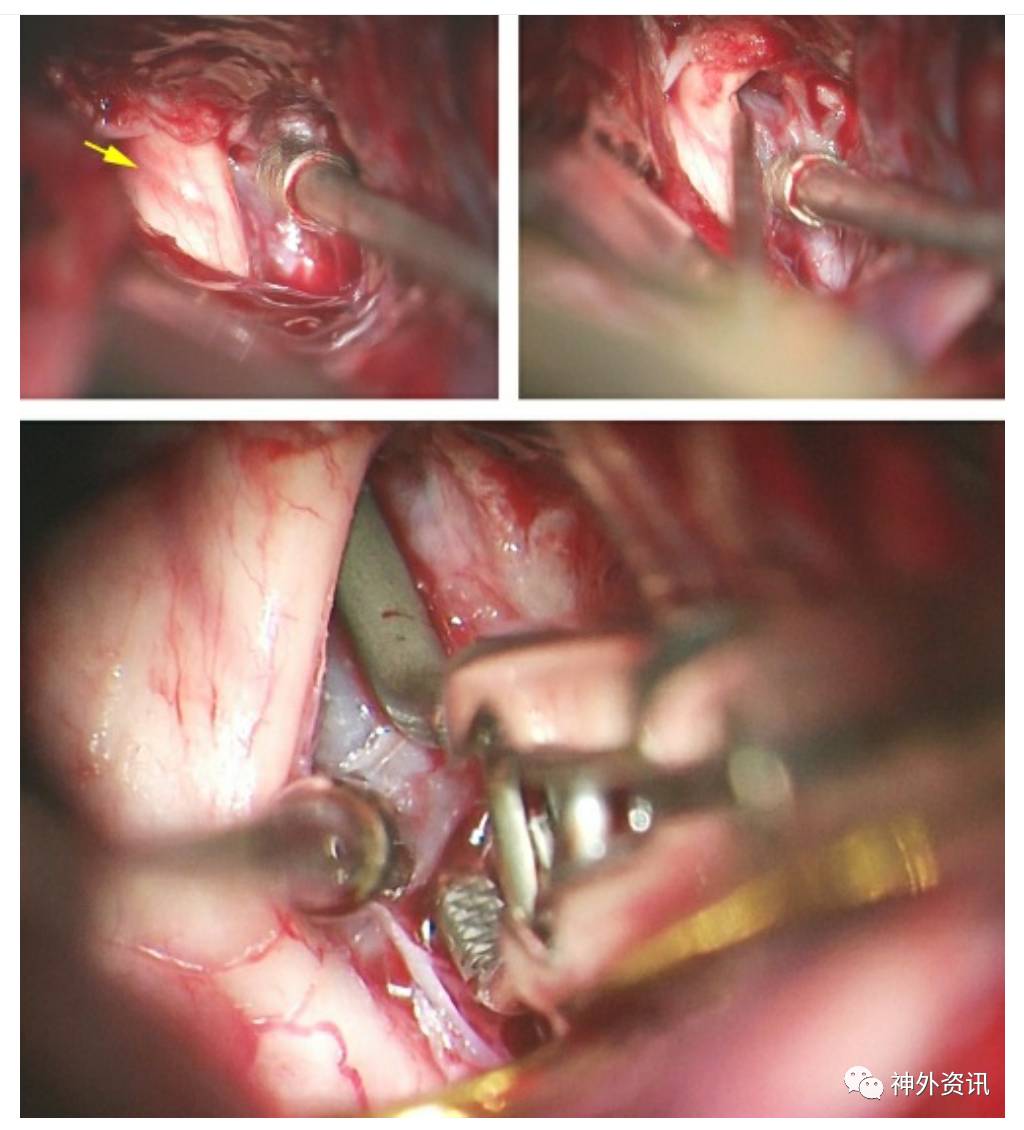

图7. 使用抽吸减压技术夹闭一个大型右侧眼动脉动脉瘤(见下图)。镰状韧带切开后可以看到因动脉瘤的占位效应引起的视神经颜色改变(左上图像,黄色箭头)。抽吸减压技术可以使动脉瘤缩小到需要的程度,因此可以识别瘤颈前部(右上图)和放置永久夹(下图)。